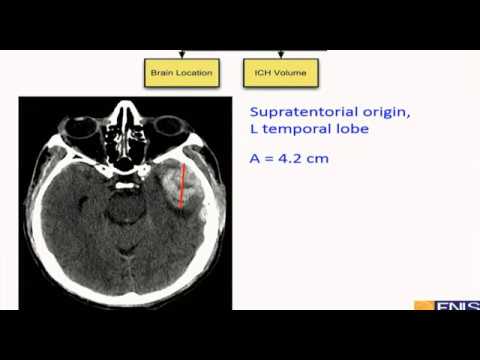

Геморрагический инсульт(Intracranial hemorrhage) Gene Yong Sung USA 2019